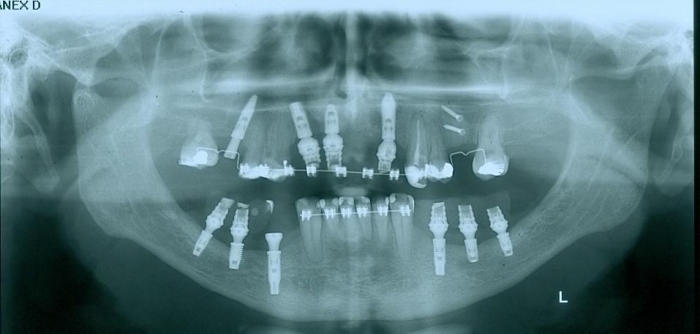

Enxerto em maxila em Fevereiro de 2012 - Clínica Cliniface

Enxerto em maxila em Fevereiro de 2012